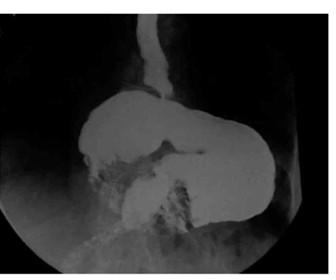

האבחנה נקבעת חד-משמעית על-ידי שיקוף דרכי העיכול העליונות, לאחר מתן חומר ניגוד. דרך זו נמצאה יעילה גם במקרים הכרוניים, אם כי לעתים די בצילום סקירה של בית החזה כדי להעיד על קיום פתלת הקיבה (תצלום 30.3).

| תצלום 30.3: פתלת הקיבה (צילום קיבה עם מילוי בריום – קיבה הפוכה) | |